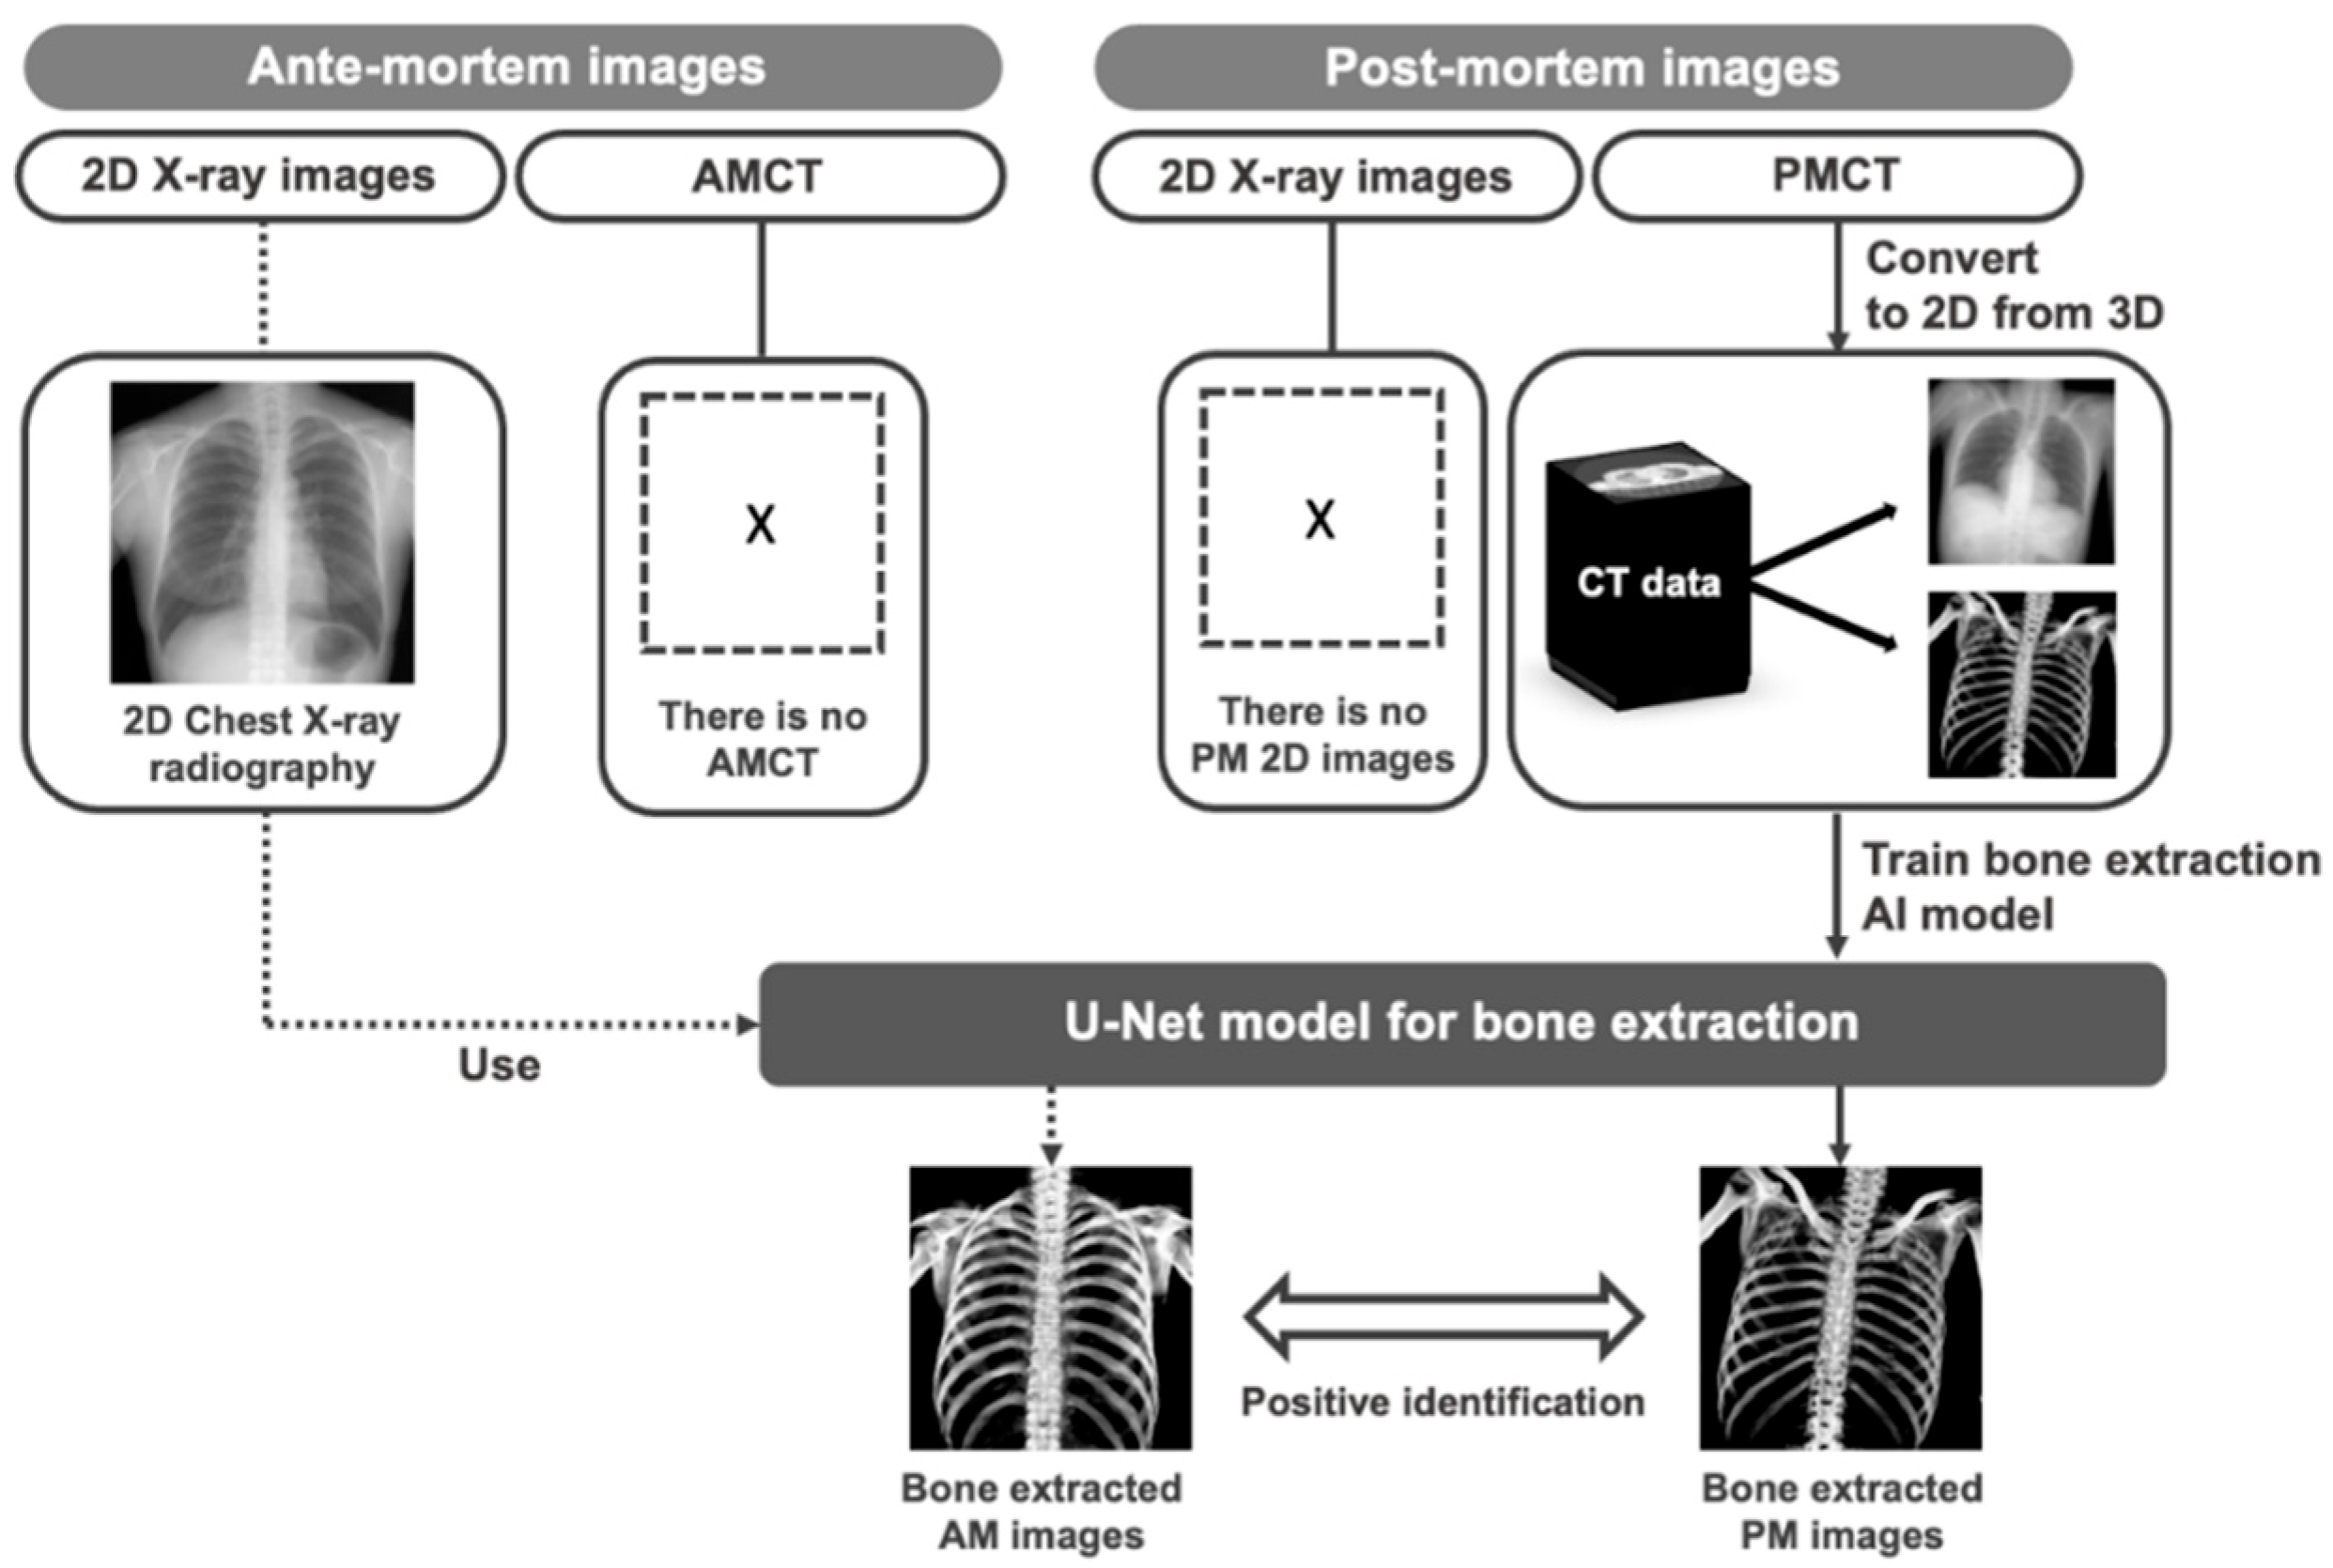

2.1. Overview of Proposed Method

2.2. Image Database

2.3. Pre-Processing: Producing Training Datasets from PMCT Images